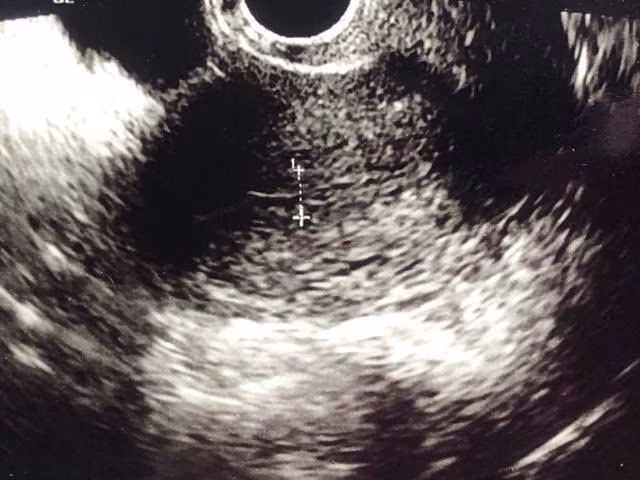

高中生每天吃「2食物」得脂肪肝!醫照超音波嚇傻:整塊肝變白